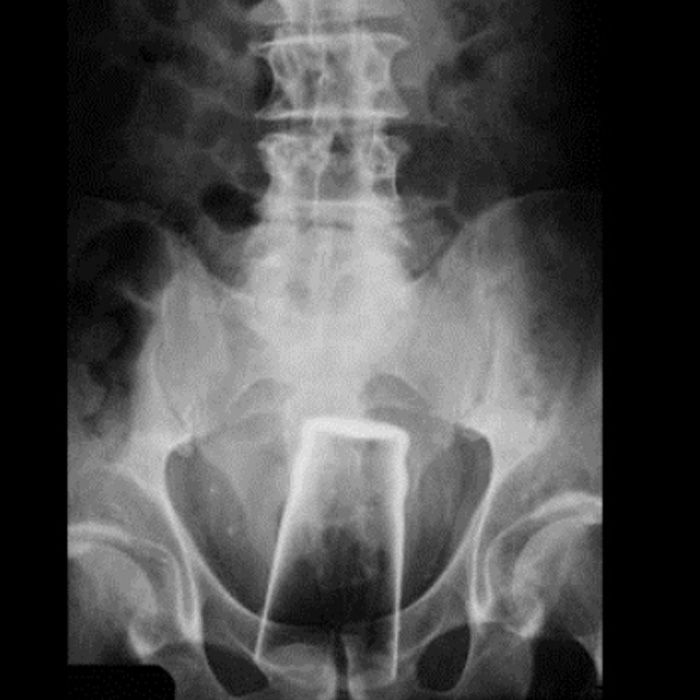

No, no, no, no! Listen! I’m definitely not saying that the Coronavirus has been A Good Thing™, I’m not denying that it’s been a horrible uplifting of what we all once accepted as society and has forced radical rethinks of ways of living and desperate self evaluation of perhaps the entire population of the globe. But- but, but, but!- the reaction to it among ordinary people has, by the large, been quite beautiful. We have all accepted that we need to wear masks, wash out hands and be generally considerate of those around us. We have accepted the enforced reimagining of ‘normal’ and all done our part. This is a virus that, remember, will not have fatal effects on maybe 95% of us. That means 95% of us are not really doing all of this to protect ourselves, but to ensure the safety of the most vulnerable. Yeah, I know, you saw on your Facebook feed how one Karen in Oklahoma made a scene in Target, or how a group of people are exercising outside their gym in protest to… prove.. they can… exercise… without a gym…? Whatever, you need to look beyond your newsfeed of the most shocking and clickably disgusting examples of the outskirts of humanity and accept that’s not the ‘real’ world. We all watched that CCTV video of the drunk guy in Great Yarmouth sticking a pint glass up his bum after being thrown out of Wetherspoons, but that doesn’t mean everyone in Yarmouth is doing that!! I’ve been to Great Yarmouth, the majority of people don’t do that! The vast majori… Well, maybe not the vast majority, but most people definitely don’t!!